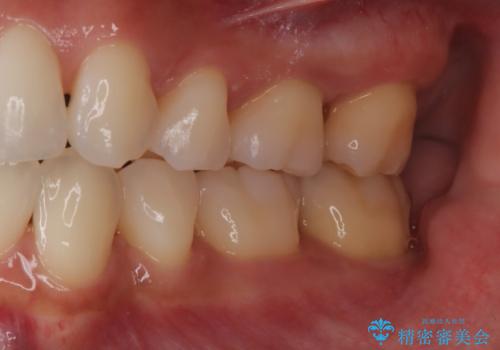

歯周ポケットがそれほど深くない患者さんでしたが、いざ歯茎を開いてみるとそこにはたくさんの歯石がありました。もし歯周ポケットが4ミリだからと言って放置していれば数年後には、沢山の骨が無くなっていたことが予期出来ます。現段階で歯茎の下にある歯石を除去することにより骨が無くなることを予防する事が出来ました。